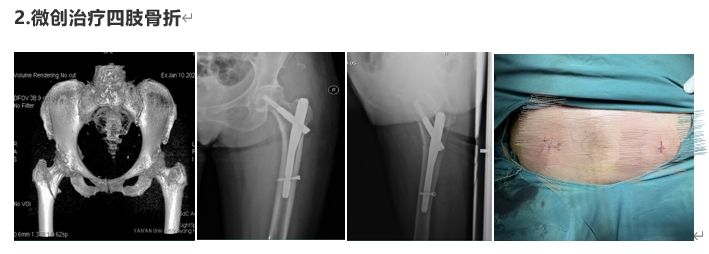

部分病例展示

延安大學(xué)咸陽醫(yī)院骨科二病區(qū)是以手足顯微外科、慢性創(chuàng)面修復(fù)、關(guān)節(jié)外科、創(chuàng)傷骨科、小兒骨科為主要研究方向的專業(yè)化科室?,F(xiàn)有床位36張,醫(yī)護(hù)人員20人,其中主任醫(yī)師1名,副主任醫(yī)師2名,中級(jí)職稱3名,住院醫(yī)師2名。